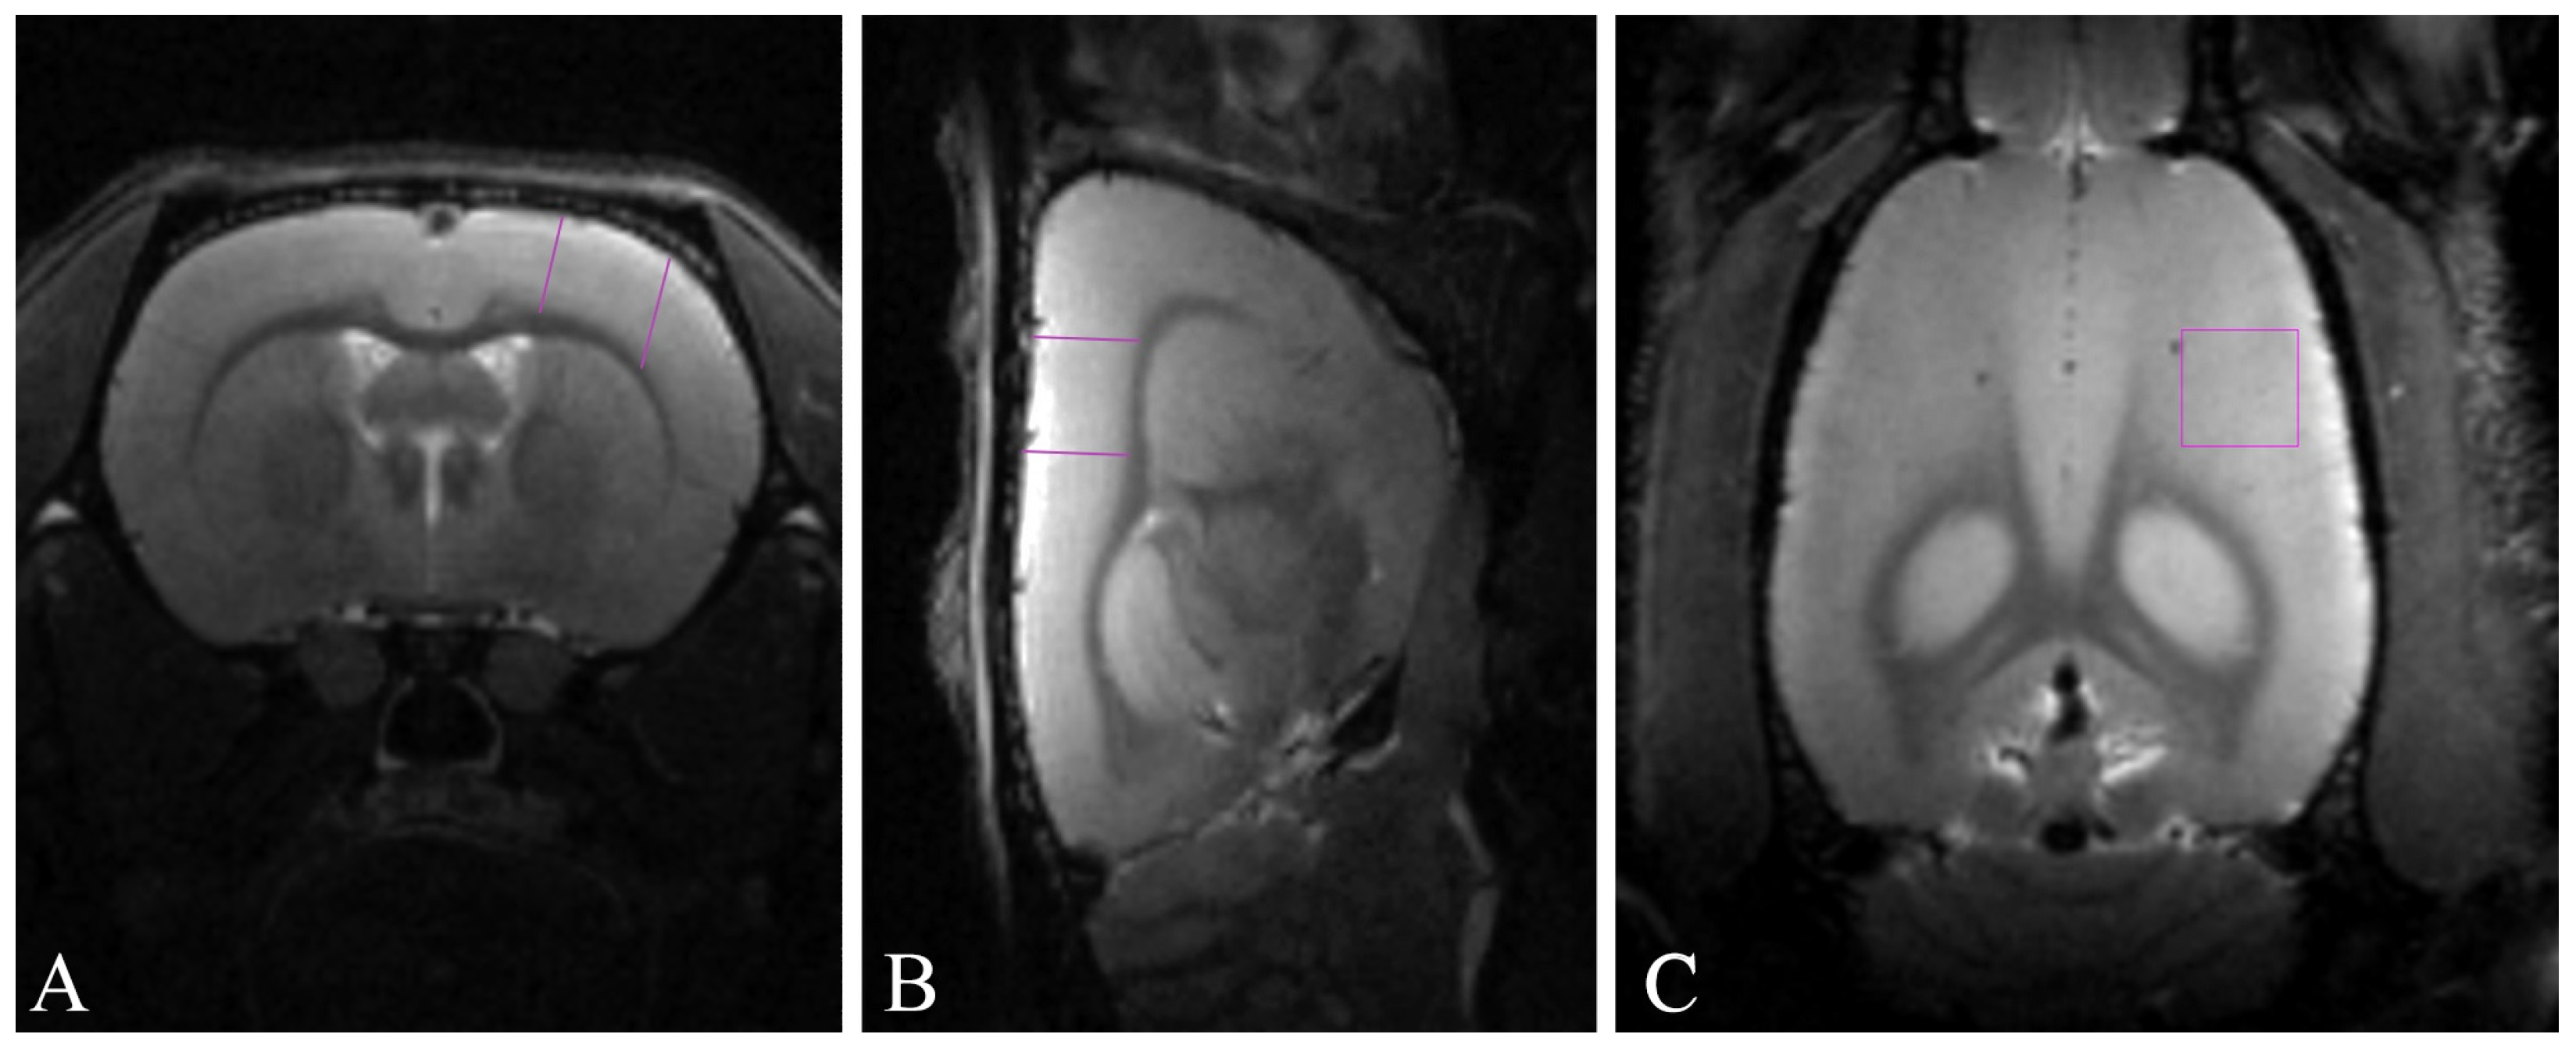

The cortical area whose volume was precisely estimated (Figure 5) included the primary motor cortex (M1) and the primary somatosensory cortex (three zones: S1FL, S1HL, and dysgranular S1DZ; the sensorimotor cortex). To identify the target area of the neocortex, we employed data from both the in vivo rat atlas by Schwarz et al. [75] and the rat brain atlas by Paxinos and Watson [76].

Figure 5.

Representative T2-weighted MR images of rat brain with analysis area highlighted by purple lines: (A) axial projections; (B) sagittal projections; (C) coronal projections.